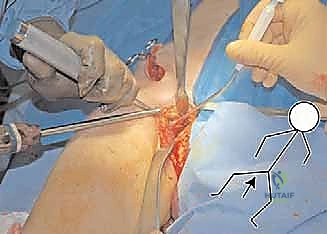

3. مرحلة القطع العظمي (The Three Osteotomies)

هنا تكمن عبقرية الإجراء. يتم استخدام مناشير جراحية دقيقة لعمل قطوع في:

* عظم الإسك (Ischium): العظم السفلي الخلفي للحوض.

* عظم العانة (Pubis): العظم الأمامي للحوض.

* عظم الحرقفة (Ilium): العظم العلوي العريض للحوض.

بمجرد اكتمال هذه القطوع الثلاثة، يصبح التجويف الحقي (الكوب) منفصلاً تماماً عن بقية الحوض، مع بقاء إمداداته الدموية سليمة.

4. إعادة التوجيه والتدوير (Rotation & Redirection)

باستخدام أدوات خاصة، يقوم الدكتور هطيف بتدوير التجويف الحقي الحر في ثلاثة أبعاد (للأمام، وللخارج، وللأسفل) حتى يغطي رأس عظم الفخذ بشكل مثالي وميكانيكي سليم. يتم التحقق من الزاوية الجديدة فوراً داخل غرفة العمليات باستخدام جهاز الأشعة السينية المتحرك (C-arm).